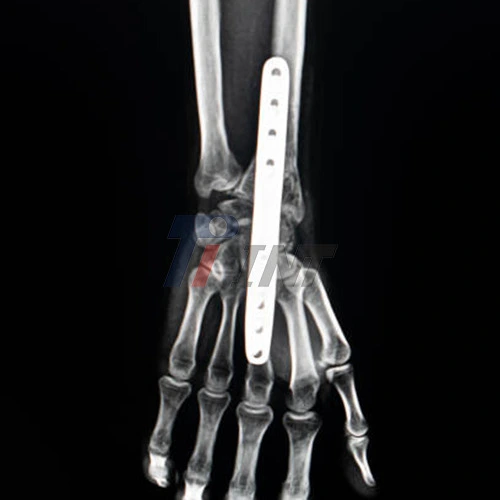

Titanium plates are habitually utilized in wrist surgeries due to their surprising properties. These biocompatible implants give steadiness to the broken bones, permitting them to mend appropriately. Titanium's strength-to-weight proportion is unparalleled, making it a perfect fabric for orthopedic inserts. The plates are planned to withstand the stresses of every day exercises whereas advancing bone mending.

Attend all scheduled follow-up appointments with your surgeon. These visits allow your doctor to assess your healing progress, check the position of the titanium plate in wrist surgery, and address any concerns you may have. X-rays may be taken to evaluate bone healing and ensure the plate is properly positioned.